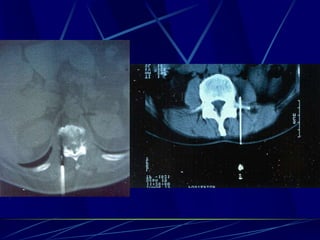

Φυματίωση της σπονδυλικής στήλης